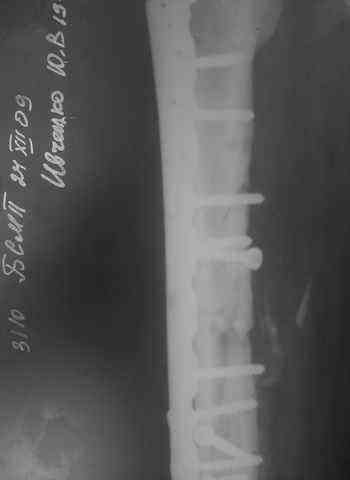

Несрошийся открытый фрагментарный, оскольчатый, перелом в/с/3 правого бедра с размозжением мягких тканей.

Состояние после ПХО,МОС,ВО ЧКФ стержневым АВФ.

Операция:16.12.09,открытый накостный МОС,аутокостная пластика(из крыла подвздошной кости)правого бедра. После п/о периоде заживление раны вторичным натяжением (на 5-е сутки распущены швы, после очищения раны наложины вторичные швы) На этапных RO-гр:остеолизис костного трансплантата и дистального фрагмента перелома бедра.